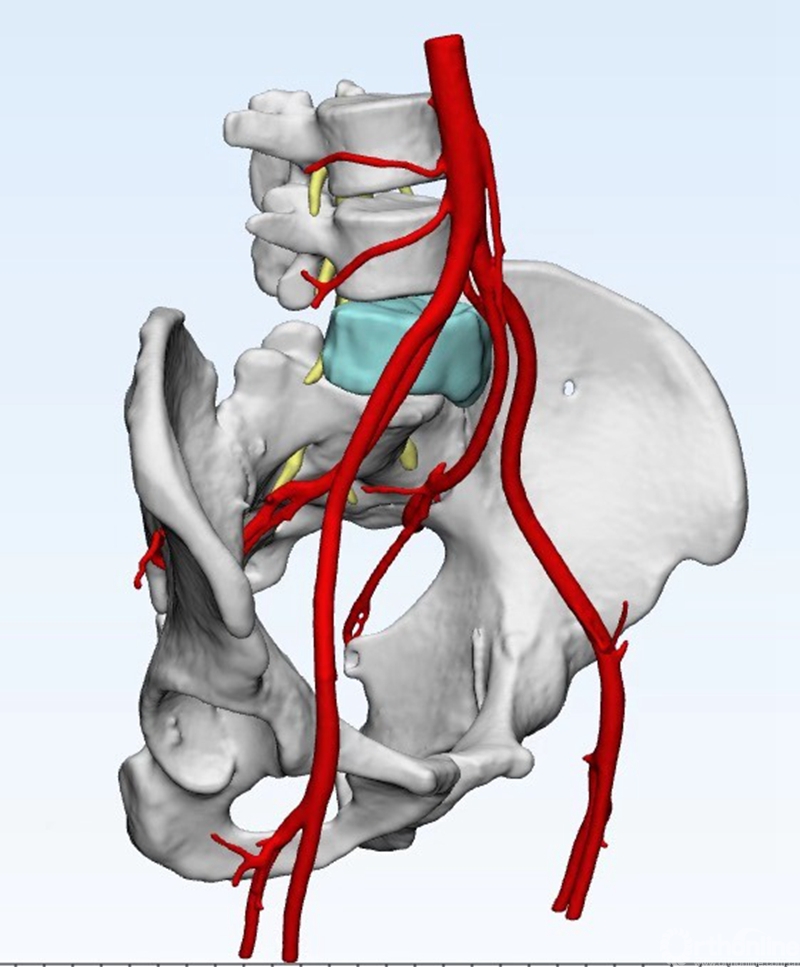

术前CT三维重建

经过多次讨论后,李锋教授团队决定联合应用“3D打印+混合现实+计算机辅助导航”三大前沿技术,为患者量身定制微创化、个性化、精准化的治疗方案。

术前4天,李锋教授团队根据患者的原始影像学资料,利用3D打印技术将患者病灶模型打印出来。李锋教授立即带着模型到病房为患者“再现”病灶环境,详细讲解了手术方案。有了直观的模型,患者对自己的肿瘤位置及手术方案能够一目了然,心里踏实。

术前2天,李锋教授通过3D技术为患者定制了个性化人工椎体,这个椎体将在肿瘤切除后,植入到患者的腰椎上,代替被肿瘤侵蚀的椎体。

3月6号,手术正式开始。李锋教授戴着虚拟眼镜,通过简单的几个手势操作,将田先生病灶模型和人工椎体模型的虚拟3D影像跟田先生的真实腰椎吻合,以便更精准的切除肿瘤。再将患者变换多个体位后,包含肿瘤的第五腰椎终于被整块切了下来。

固定人工椎体时,李锋教授一边使用计算机辅助导航设备在田先生脊柱上探测、一边抬头看手术床尾的计算机屏幕,依据屏幕显示来导航,精准定位、寻找合适的植钉位置。